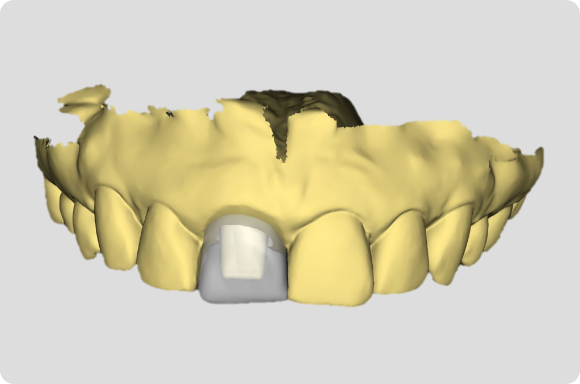

Utilising procedure-based education1, this level will help the clinician grow into more advanced surgical and prosthetic concepts with the treatment of single tooth anterior implant cases

Throughout this level, the cases will cover topics including: Evaluating buccal and apical bone for immediate placement, Grafting around immediate implants (Dual Zone Technique), Defining implant orientation – The Rules of Six, Assessing primary stability for immediate provisionalization, CAD/CAM abutment options and designs. At the completion of this level, participants will understand how to place and restore a single-tooth implant in the anterior zone. Participants are encouraged to continue their education in Level 4, which will focus on multi-unit cases.